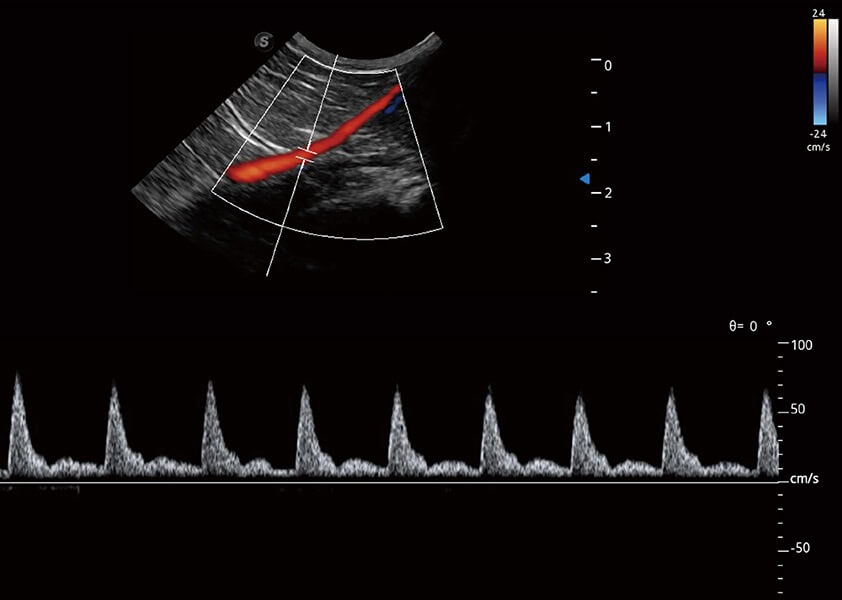

ProPet 60 作为一款高端台式动物超声设备,为动物医生的日常诊断提供了一系列贴合动物临床需求、解决临床实际问题的高级成像功能。凭借全系列高清探头,满足医生对腹部、心脏、生殖、浅表、肌骨等成像的所有需求,切实帮助您提升检查效率,提高诊断信心。

ProPet 60 尊享版

兽用彩色多普勒超声诊断系统